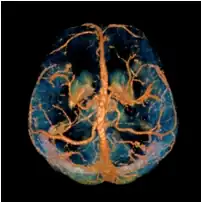

A volume rendered brain QSM acquired at 3 Tesla and reconstructed with morphology enabled dipole inversion (MEDI).

Morphology enabled dipole inversion (MEDI)

A unique advantage of MRI is that it provides not only the phase image but also the magnitude image. In principle, the contrast change, or equivalently the edge, on a magnitude image arises from the underlying change of tissue type, which is the same cause for the change of susceptibility. This observation is translated into mathematics in MEDI,[13] where edges in a QSM which do not exist in the corresponding magnitude image are sparsified by solving a weighted norm minimization problem.[14]

MEDI has also been validated extensively in phantom, in vitro and ex vivo experiments. In an in vivo human brain, MEDI calculated QSM showed similar results compared to COSMOS without statistically significant difference.[15] MEDI only requires a single angle acquisition, so it is a more practical solution to QSM.